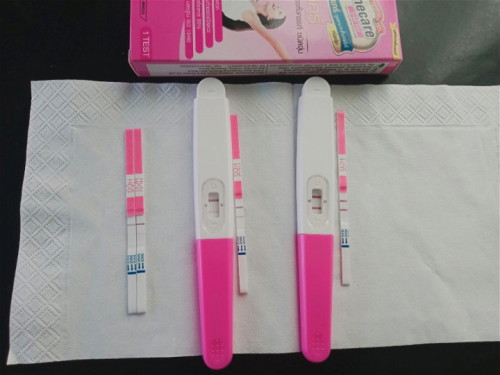

จากที่ก่อนหน้านี้โพสว่ามีเลือดน้ำตาลซึมออกและซาวด์ยังไม่เจอตัวน้อง ล่าสุด13-01-67ไปซาวด์รอบ2 #เจอตัวน้องพร้อมเสียงหัวใจแล้วนะคะ แม่กับคุณพ่อยิ้มหน้าบานทะลุแมสเลยค่ะ วัดจากเครื่องซาวด์8วีค2วัน นับจากประจำเดือน 7วีค5วัน รอบนี้เกาะแม่แน่นๆนะลูก

ประจำเดือนล่าสุด วันแรก17- 21/12/2566

23-26/12มีมูกเลือดน้ำตาลเข้มแล้วหาย ถัดมาอีก3วันมีมูกน้ำตาลออกวันนึง ล่าสุดวันนี้02-01-67 ไปพบหมอ #อัลตร้าซาวด์หน้าท้องเจอแค่ถุงตั้งครรถ์ หมอแจ้งว่าดูจากถุงตั้งครรภ์น่าจะ5สัปดาห์ อีก2อาทิตย์ไปซาวด์ใหม่ถ้ารอบหน้าเจอตัวเด็กและหัวใจก็ค่อยฝากท้อง ในใจแม่ก็แอบหมดหวังแล้วค่ะ คิดว่าคงจะแท้งเหมือนรอบที่แล้วเพราะอาการเหมือนกันเลย 😔